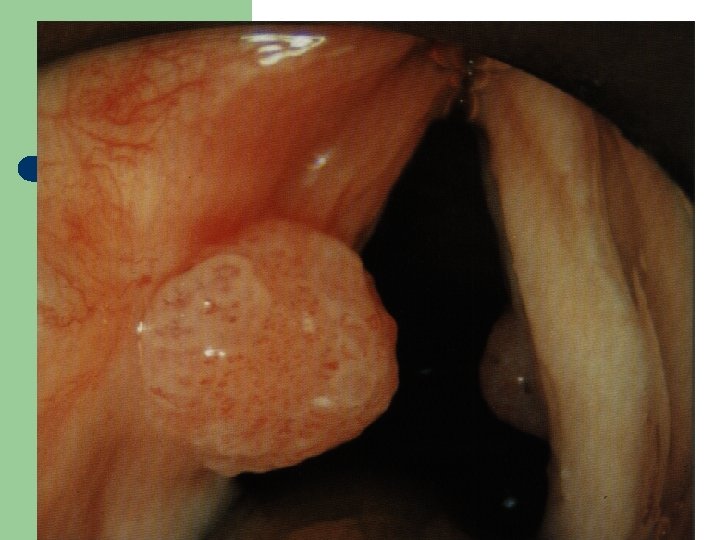

Hlasivkový uzlík l

Hlasivkový uzlík l